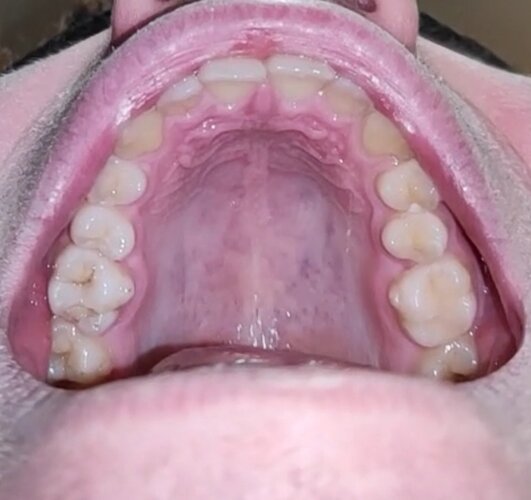

My palette is 35 mm at 15 y.o. Should I Get MARPE?

• IMG_20251230_111044_678.jpg

IMG_20251230_111044_678.jpg